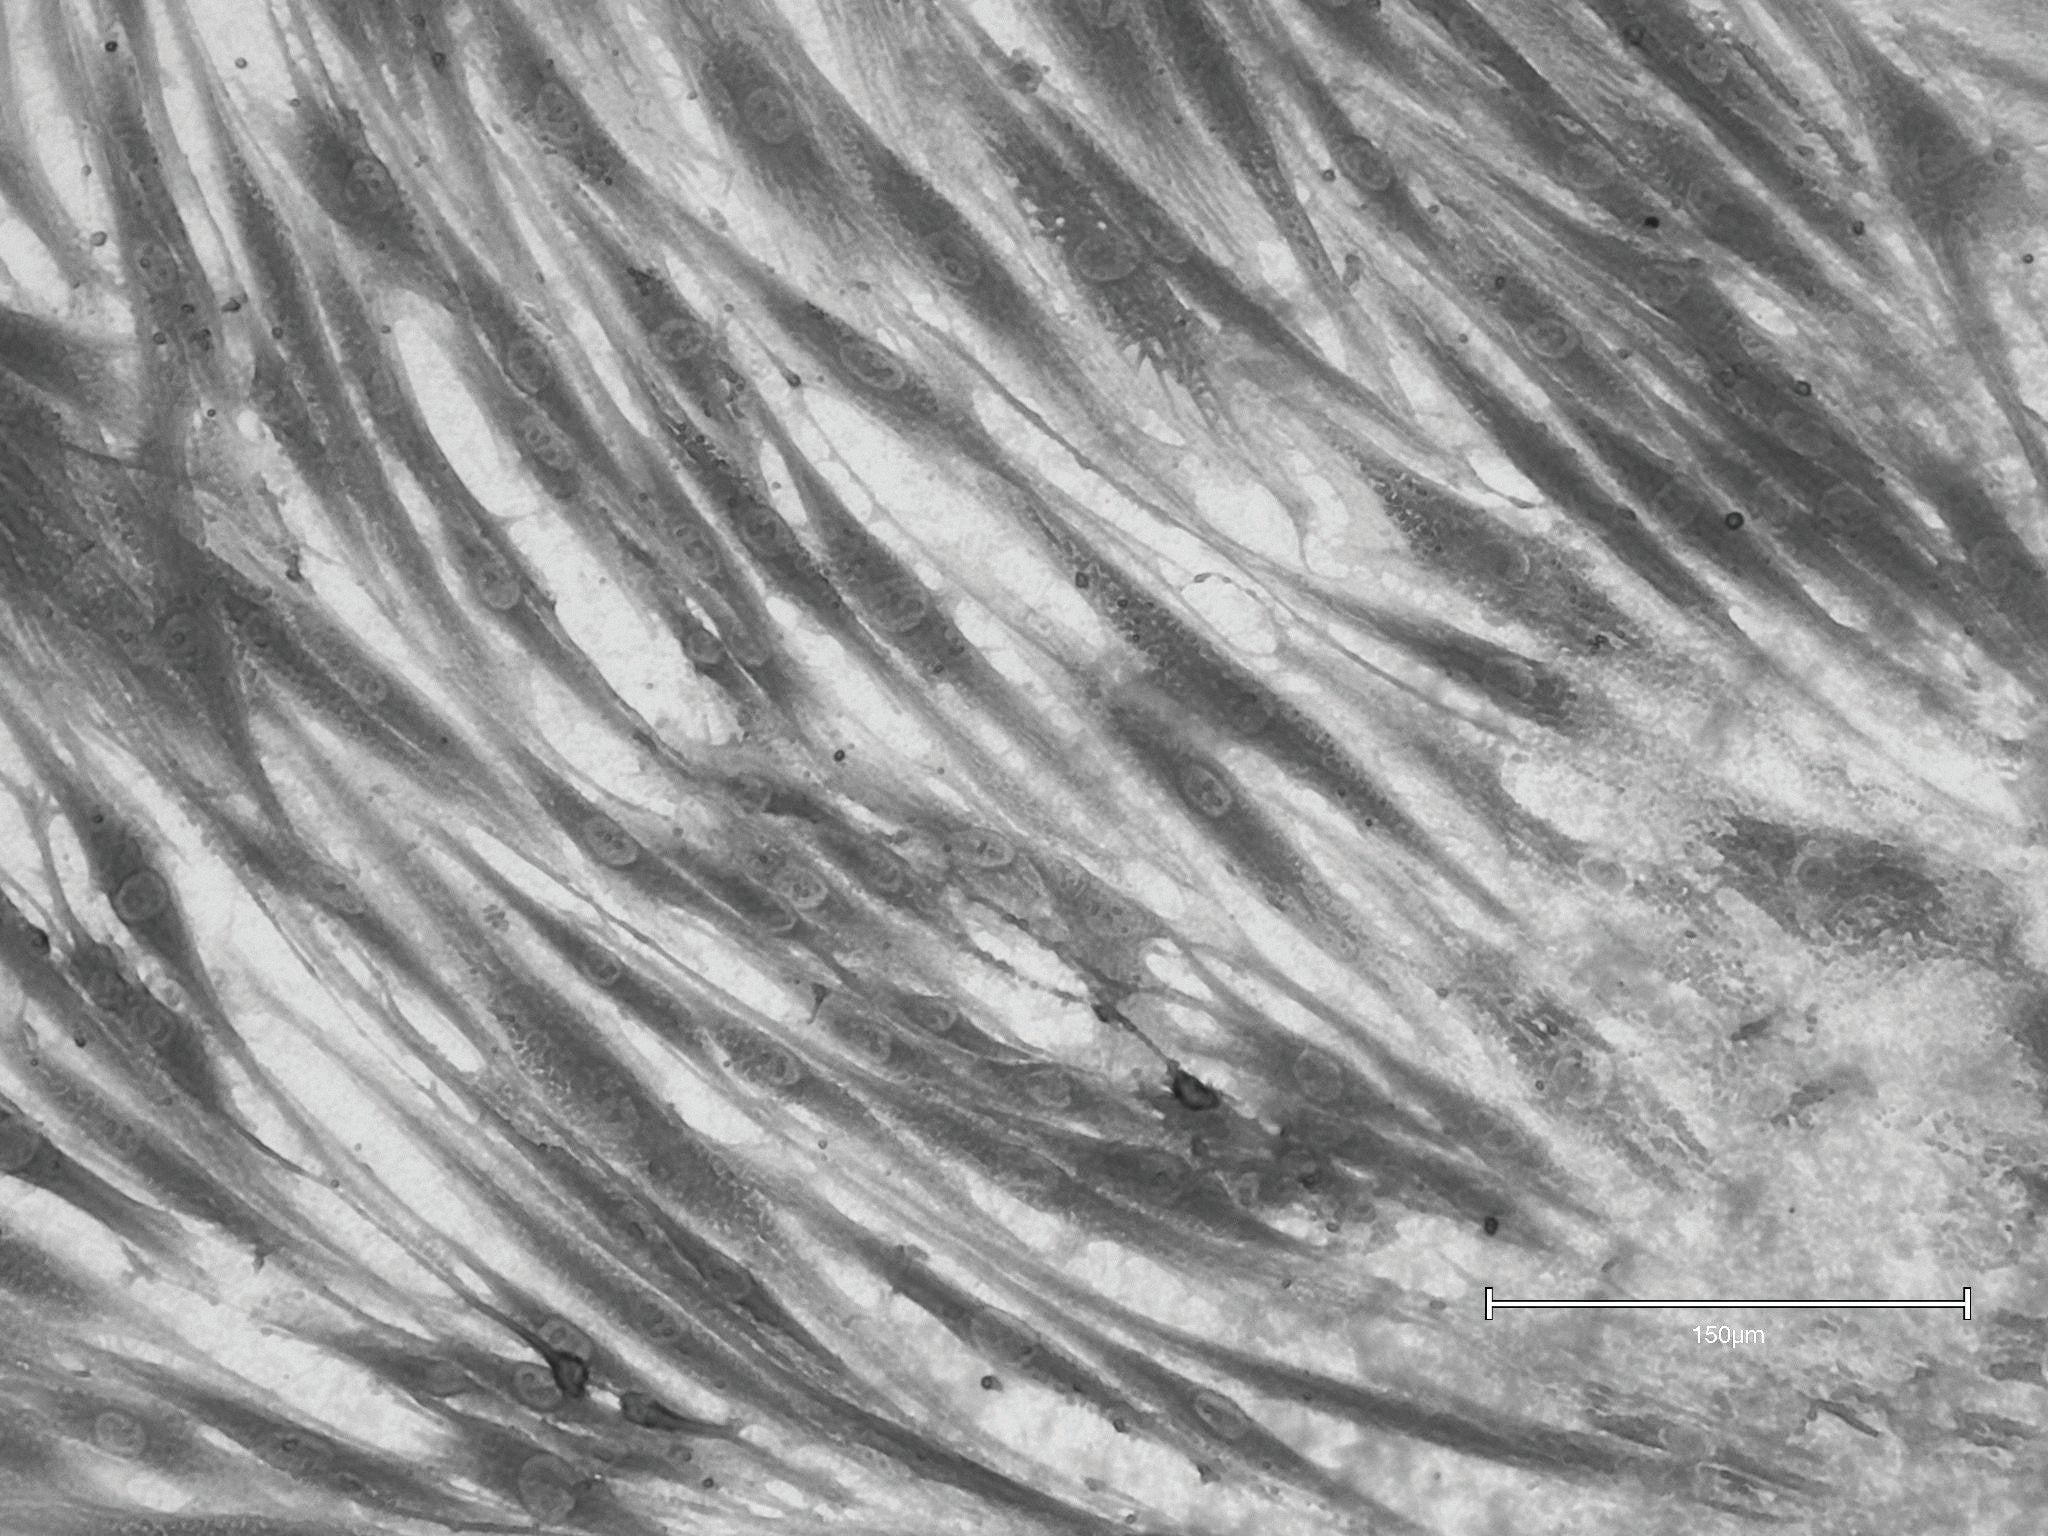

RLX-201 Treated

Cultured fibroblast from abdominal skin treated with RLX-201; fibroblast cells were observed to be more elongated post treatment, metabolically active, and healthier